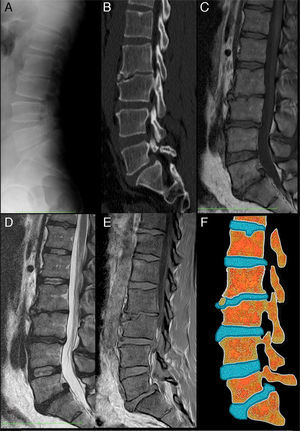

Varón de 39 años, agricultor, sin antecedentes de interés, con lumbalgia mecánica crónica limitante, sin irradiación, fiebre ni cuadro constitucional. En la exploración, solo destacó palpación dolorosa de espinosas lumbares y flexión dorsal anterior limitada. Los reactantes, serologías y proteinograma fueron normales. La radiografía de columna lumbar (fig. 1a) mostró lesión irregular esclerótica-lítica en epífisis L3. Se realizó TC lumbar (fig. 1b), con irregularidad, aplastamiento y fragmentación a nivel anterior de L3. La RM de columna lumbar (figs. 1c-e) evidenció vértebra limbus (VL) L3, discopatía degenerativa L2-L4, L5-S1 y hernias discales L3-L4 y L5-S1.

Vértebra limbus: a) Radiografía lateral de columna lumbar. Se aprecia irregularidad de la esquina superior y anterior del cuerpo vertebral L3. El espacio intervertebral L2-L3 se encuentra estrechado. Se observan pequeñas formaciones osteofitarias anteriores en L2 y L4. La densidad de los cuerpos vertebrales se conserva; b) TC con reconstrucción MPR sagital, donde se observan con mayor detalle la irregularidad del borde súpero-anterior del cuerpo L3, apreciándose esclerosis tanto en el platillo vertebral hundido como en los contornos del fragmento óseo separado del resto del hueso. También se observa una listesis L5-S1 y una hernia de Schmorl en el platillo superior de L1; c) RM secuencia SET1 en el plano sagital. La intensidad de los cuerpos vertebrales está conservada y el fragmento óseo separado del cuerpo L3 presenta la misma intensidad de señal que el resto del hueso; d) RM secuencia SET2 en el plano sagital. Los hallazgos complementan lo observado en la secuencia SET1. Se observa disminución de altura y señal de los discos intervertebrales L2-L3, L3-L4 y L5-S1 en relación con deshidratación en el contexto de una discopatía degenerativa. En L5-S1 se observa, también, una hernia discal posterocentral migrada cranealmente, acompañando a la listesis; e) Secuencias de RM en el plano sagital SET1 en fase y fase opuesta. En estas secuencias la señal del cartílago discal es alta y brillante. Se puede apreciar cómo se introduce entre el fragmento óseo y la región más anterior del platillo superior de L3, y f) Esquema que representa los cambios observados en las imágenes de la izquierda. Nótese como el disco intervertebral L2-L3 se introduce a través de la superficie anterior del cuerpo vertebral L3. También se puede ver una herniación de Schmorl en el platillo superior de L1 y una protrusión global del disco L5-S1 con hernia discal posterocentral acompañando a la listesis L5-S1.

La VL es un hallazgo radiológico de prevalencia desconocida y significado incierto. Es un defecto óseo que afecta al margen de cuerpos vertebrales, con fragmento desprendido de morfología triangular y bordes escleróticos (fig. 1f). Se produce como herniación intraósea del núcleo pulposo a través del anillo apofisario vertebral, antes de la fusión completa del cuerpo vertebral. Su patogenia se relaciona con la hernia de Schmorl y la enfermedad de Scheuermann. La localización más frecuente es la columna lumbar y el lugar de afectación el ángulo anterosuperior seguido del anteroinferior. Las VL posteriores son menos frecuentes, pero con mayores repercusiones clínicas-funcionales por posibilidad de desplazamiento del fragmento óseo, estrechando canal raquídeo1,2.